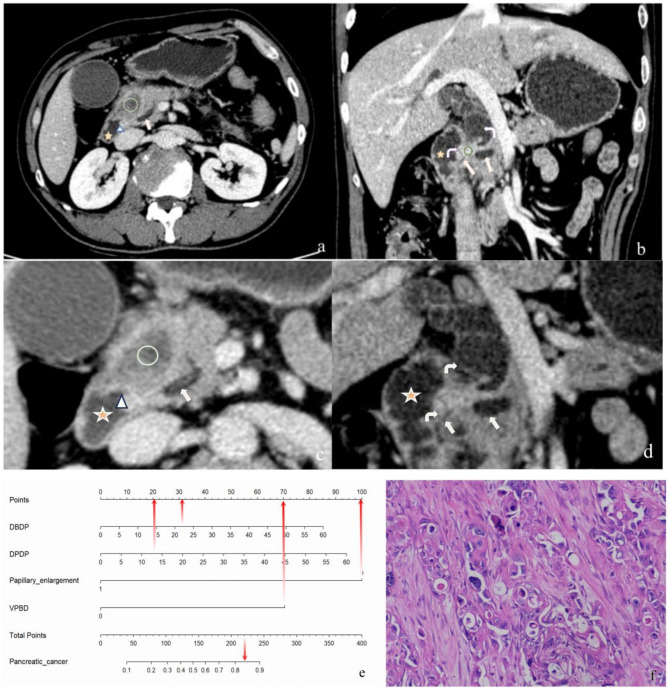

Background: To develop a predictive nomogram for differentiating pancreatic cancer from periampullary non-pancreatic cancers based on computed tomography (CT) imaging features.

Methods: This retrospective study included 171 patients diagnosed with periampullary carcinoma (90 pancreatic cancer and 81 non-pancreatic cancer). Variables assessed included CT imaging features along with relevant clinical data. Statistically significant variables were identified through multivariable logistic regression analysis, and a predictive nomogram was developed and internally validated based on these factors.

Results: Multivariable analysis identified the following independent risk factors: the distance from the distal end of the dilated pancreatic duct to the medial wall of the papilla (DPDP) (odds ratio [OR] 8.76, P < 0.05), the distance from the distal end of the dilated bile duct to the medial wall of the papilla (DBDP) (OR 31.83, P < 0.05), papillary enlargement (OR 0.03, P < 0.05), and visibility of pancreatic and/or bile ducts between the tumor and the papilla (VPBD) (OR 3.97, P < 0.05). A nomogram was constructed based on these four significant features. In both the development and validation cohorts, the nomogram demonstrated robust predictive performance, with areas under the receiver operating characteristic curve (AUCs) of 0.84 (95% CI, 0.77-0.91) and 0.81 (95% CI, 0.67-0.96), respectively.

Conclusions: This study underscores the value of CT imaging features in distinguishing pancreatic cancer from periampullary non-pancreatic cancers. The identification of key imaging markers with significant diagnostic value facilitated the development and validation of a nomogram that integrates these features, providing a more reliable tool for clinical decision-making.